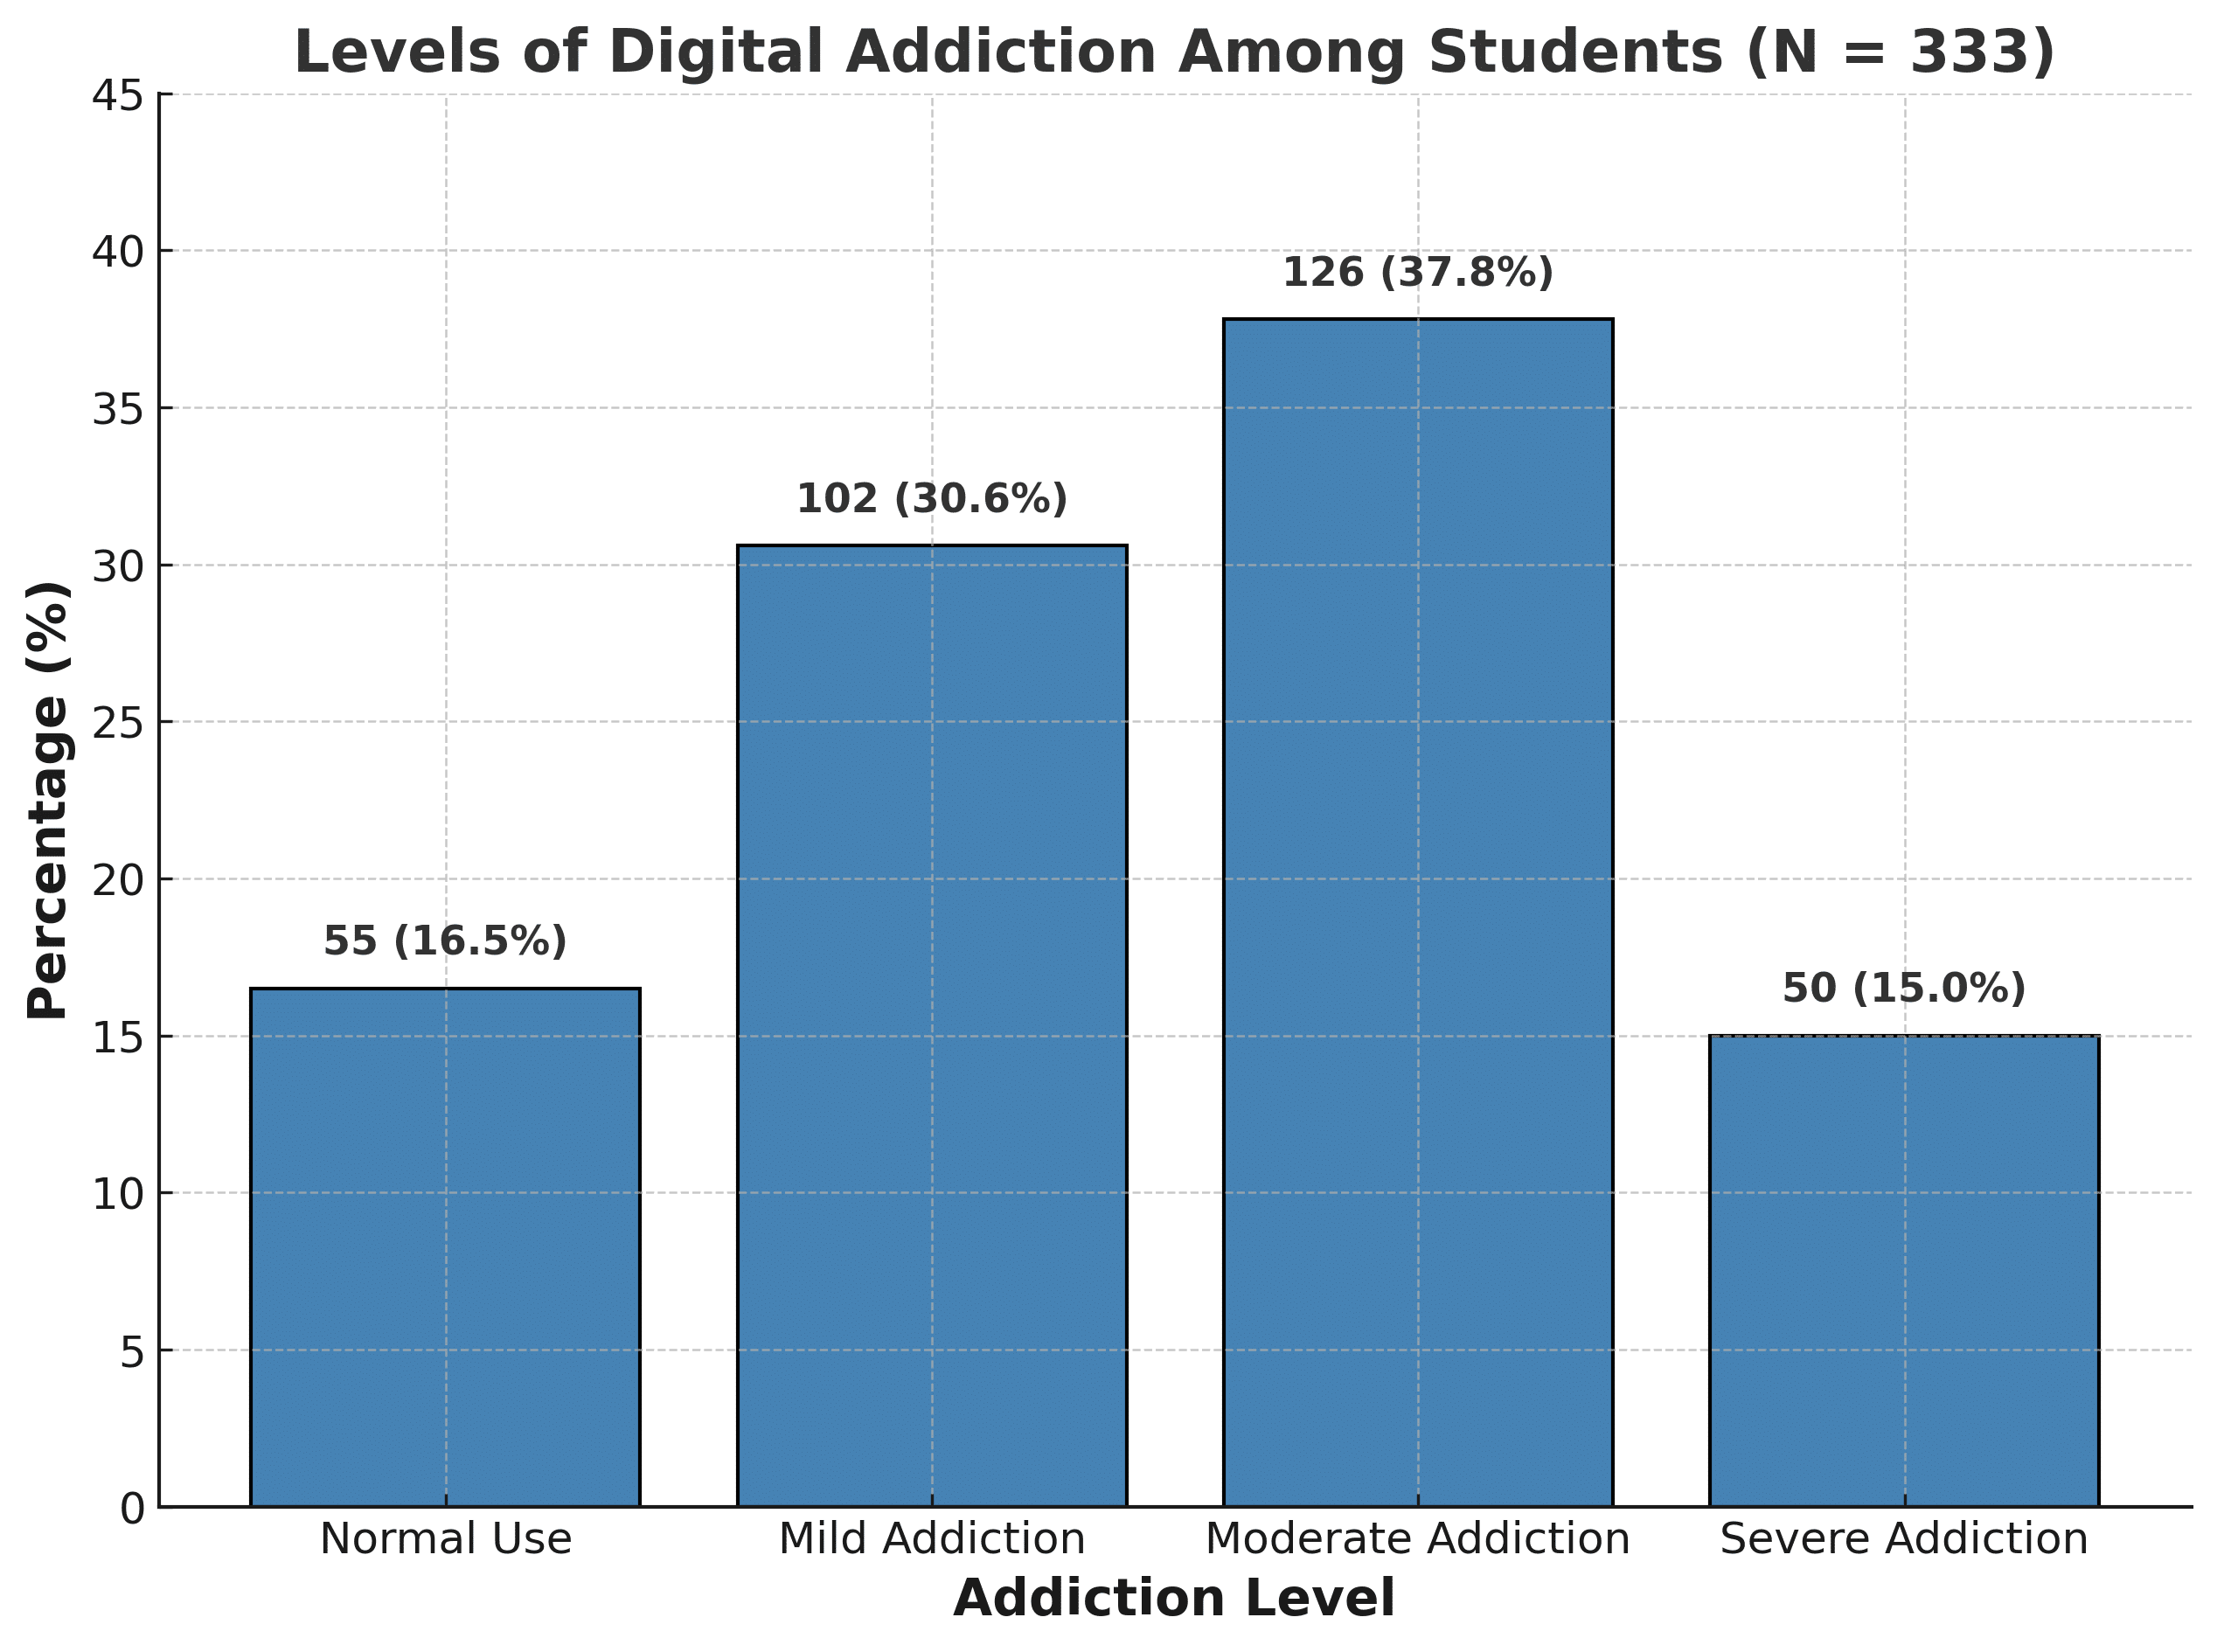

Trapped in the Screen: Clinical Insights into Digital Addiction and Mental Health Among Young Adults

Background: Digital addiction has emerged as a growing public health concern among young adults, particularly university students. Excessive digital engagement...Read More